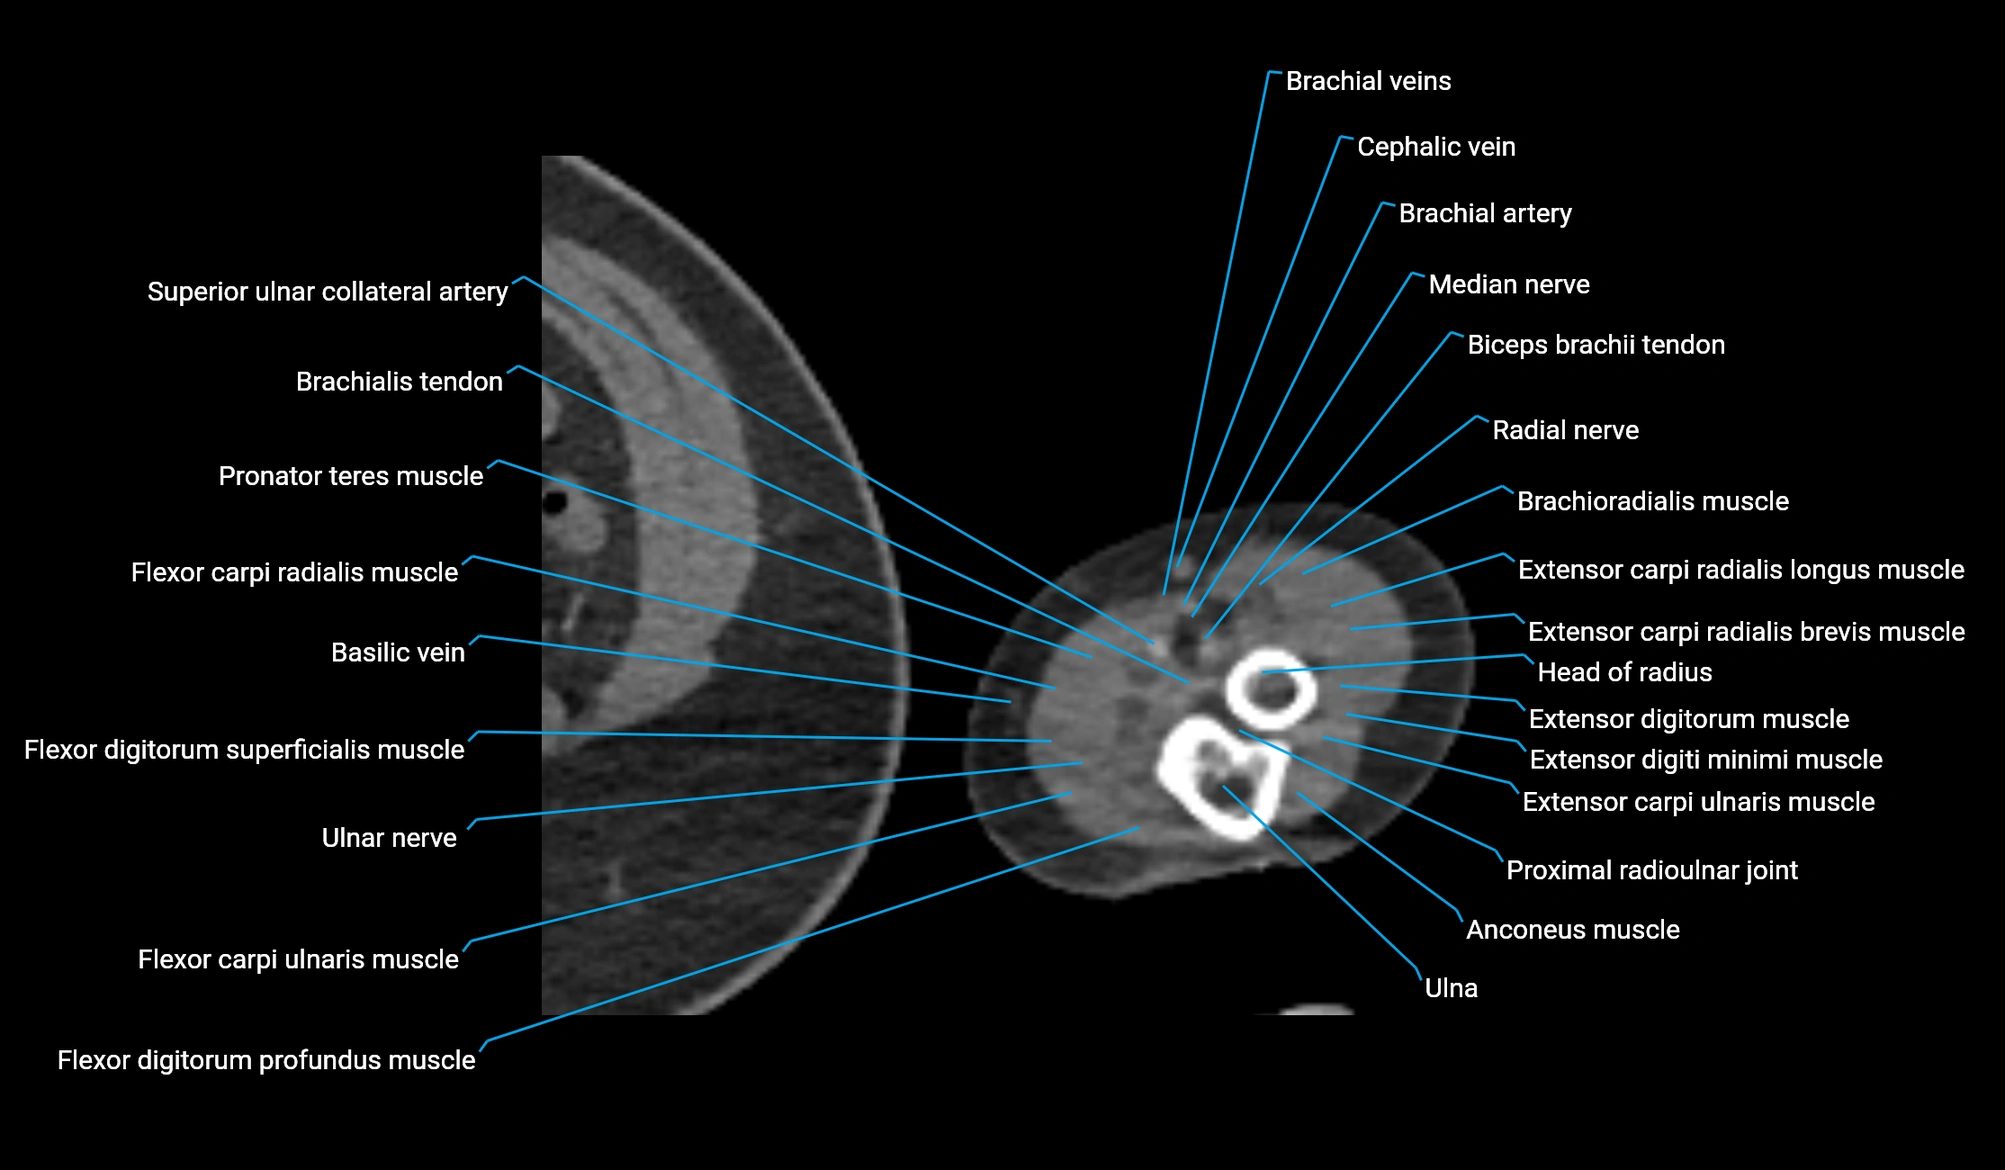

- Basilic vein

- Biceps brachii tendon (distal)

- Brachial artery

- Brachioradialis muscle

- Cephalic vein

- Coronoid process of ulna

- Extensor carpi radialis brevis muscle

- Extensor carpi radialis longus muscle

- Extensor carpi ulnaris muscle

- Extensor digiti minimi muscle

- Extensor digitorum muscle

- Flexor carpi radialis muscle

- Flexor carpi ulnaris muscle

- Flexor digitorum profundus muscle

- Flexor digitorum superficialis muscle

- Head of radius

- Median nerve

- Pronator teres muscle

- Proximal radioulnar joint

- Radial nerve

- Superior ulnar collateral artery

- Ulna

- Ulnar nerve